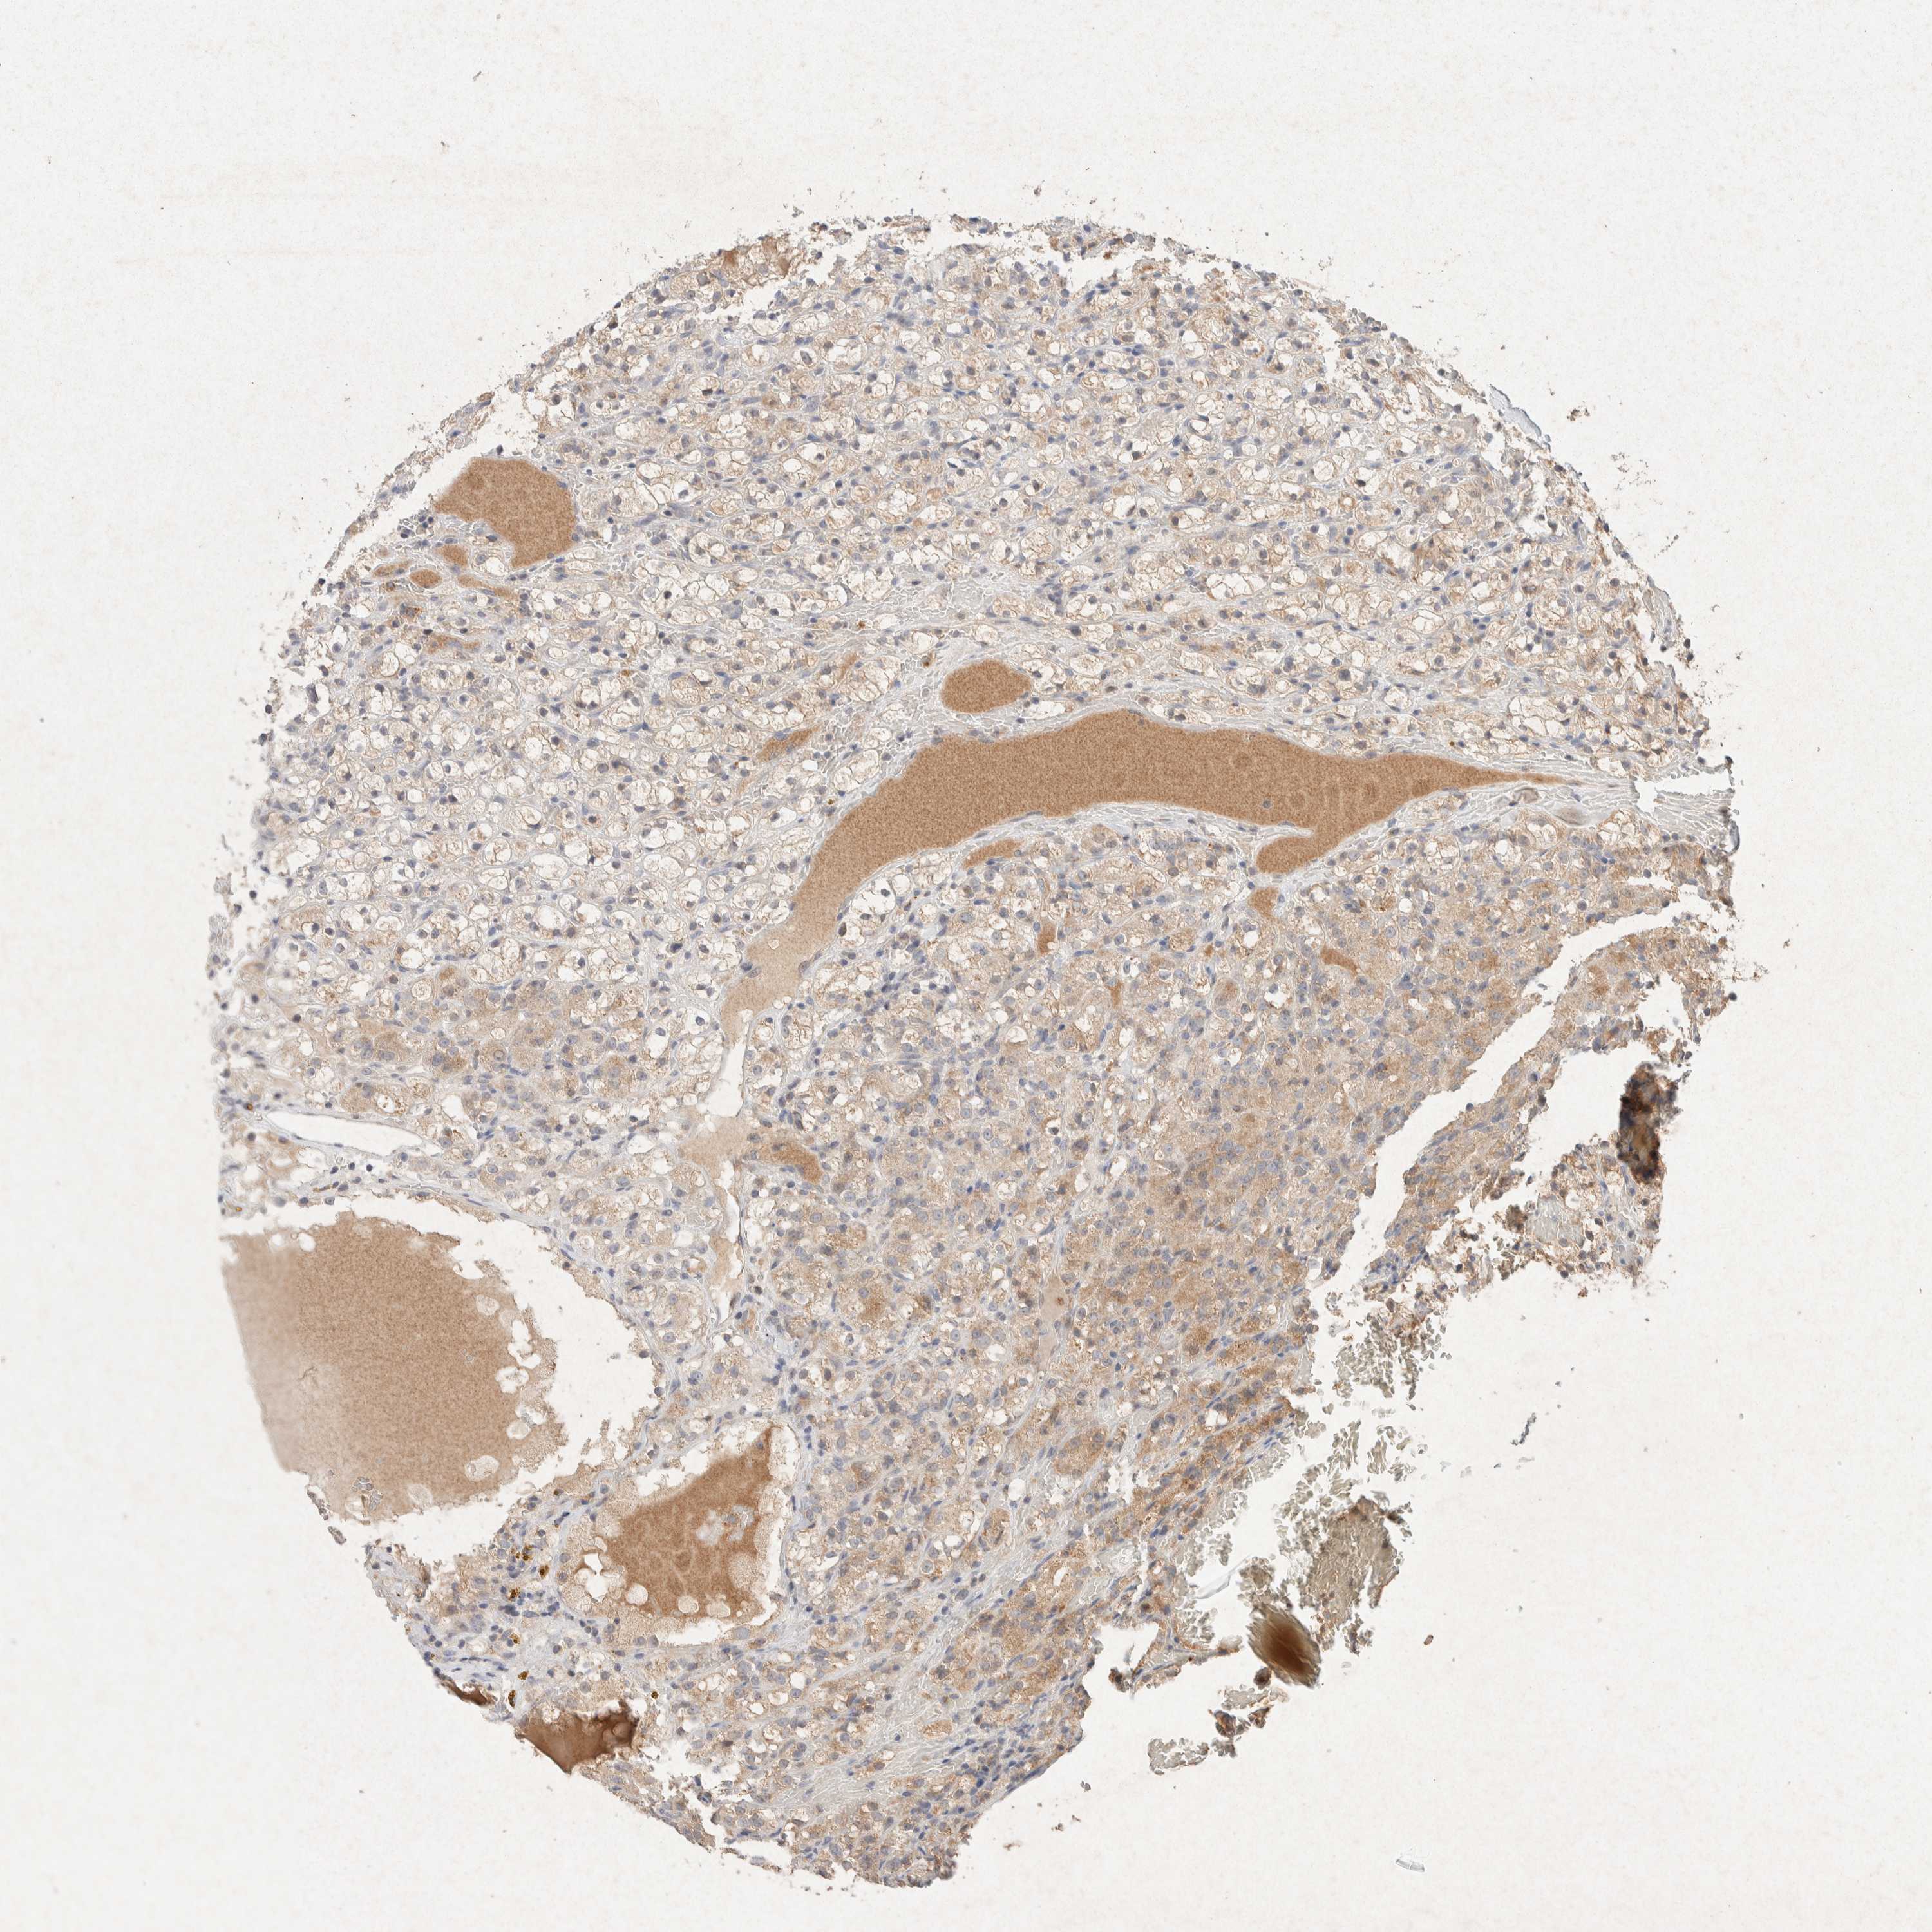

KIDNEY RENAL CLEAR CELL CARCINOMA (VALIDATION) - Interactive survival scatter ploti

The Survival Scatter plot shows the clinical status (i.e. dead or alive) for all individuals in the patient cohort, based on the same data that underlies the corresponding Kaplan-Meier plots. Patients that are alive at last time for follow-up are shown in blue and patients who have died during the study are shown in red.

The x-axis shows the expression levels (FPKM) of the investigated gene in the tumor tissue at the time of diagnosis. The y-axis shows the follow-up time after diagnosis (years). Both axes are complimented with kernel density curves demonstrating the data density over the axes. The top density plot shows the expression levels (FPKM) distribution among dead (red) and alive patients (blue). The right density plot shows the data density of the survived years of dead patients with high and low expression levels respectively, stratified using the cutoff indicated by the vertical dashed line through the Survival Scatter plot. This cutoff is automatically defined based on the FPKM cutoff that minimizes the p-score. The cutoff can be changed by dragging the vertical line or by entering a cutoff value in the square labeled "Current cut-off".

Under the Survival Scatter plot the p-score landscape (black curve; left axis) is shown together with dead median separation (red curve; right axis). Dead median separation is the difference in median mRNA expression between patients who have died with high and low expression, respectively. It is calculated as follows: median FPKM expression of dead patients with high expression - median FPKM expression of dead patients with low expression. This is intended to aid the user in visually exploring custom cutoffs and the associated p-scores and dead median separation.

Individual patient data is displayed and can be filtered by clicking on one or more of the category buttons on the top of the page. Categories describing expression level and patient information include: high, low, alive, dead, female, male and tumor stages. The scale of the x-axis can be toggled between linear and log-scale by clicking on the "x log" button. Mouse-over function shows TCGA ID, patient information and mRNA expression (FPKM) for each patient.

& Survival analysisi

Kaplan-Meier plots summarize results from analysis of correlation between mRNA expression level and patient survival. Patients were divided based on level of expression into one of the two groups "low" (under cut off) or "high" (over cut off). X-axis shows time for survival (years) and y-axis shows the probability of survival, where 1.0 corresponds to 100 percent.

GNAI1 is validated prognostic, high expression is favorable in Kidney Renal Clear Cell Carcinoma (validation)

Best expression cut offi

Based on the FPKM value of each gene, patients were classified into two groups and association between prognosis (survival) and gene expression (FPKM) was examined. The best expression cut-off refers the FPKM value that yields maximal difference with regard to survival between the two groups at the lowest log-rank P-value. Best expression cut-off was selected based on survival analysis .

When clicking on this number, the vertical dashed line indicating cut-off, the interactive survival plot, and the Kaplan-Meier curve will be adjusted to show results based on the best expression cut-off.

: 11.9

P scorei

Log-rank P value for Kaplan-Meier plot showing results from analysis of correlation between mRNA expression level and patient survival.

N/A

5-year survival highi

5-year survival for patients with higher expression than the expression cutoff.

For melanoma and glioma, 3-year survival is shown.

5-year survival lowi

5-year survival for patients with lower expression than the expression cutoff.

TCGA RNA samplesi

RNA-seq data is reported as average FPKM (number Fragments Per Kilobase of exon per Million reads), generated by the The Cancer Genome Atlas (TCGA) .

Normal distribution across the dataset is visualized with box plots, shown as median and 25th and 75th percentiles. Points are displayed as outliers if they are above or below 1.5 times the interquartile range. FPKM values of the individual samples are presented next to the box plot.

Average pTPM 10.1

Number of samples 100